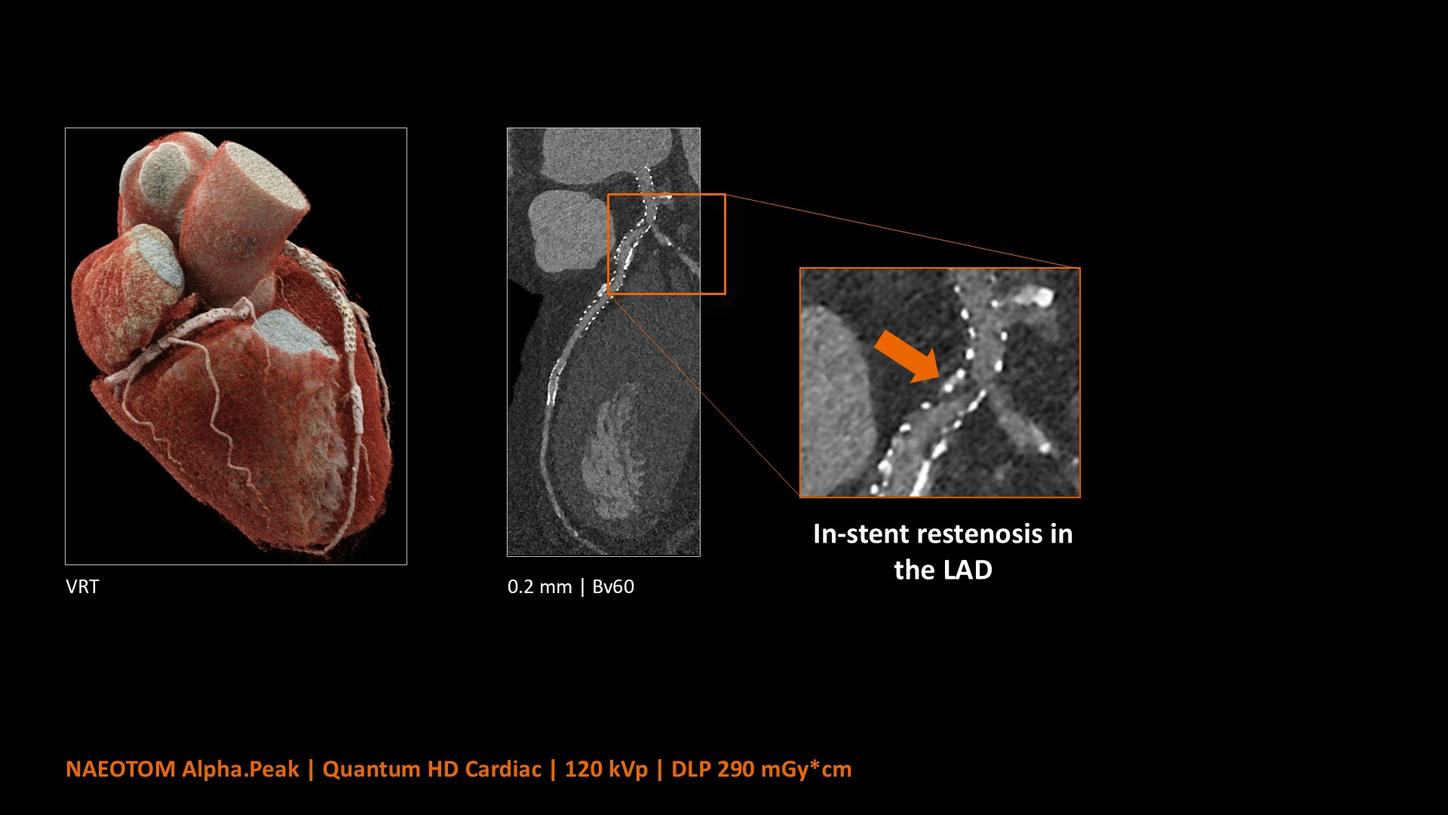

NAEOTOM Alpha® con Quantum Technology®, la nostra nuovissima Dual Source photon-counting CT, offre immagini Quantum HD Cardiac con uno spessore di slice di 0,2 mm. In questo modo è possibile visualizzare dettagli del cuore precedentemente non rilevabili senza incrementi di dose. Inoltre, le informazioni spettrali sono automaticamente disponibili in ogni scansione grazie a un processo di conversione diretta che trasforma i singoli fotoni dei raggi X in un segnale elettrico per creare l'immagine.

Quantum Technology consente una migliore valutazione diagnostica dei vasi coronarici nella TC. Secondo un recente studio, NAEOTOM Alpha e Quantum HD Cardiac potrebbero aver contribuito a ridurre la necessità di un'angiografia coronarica invasiva per il 54% dei pazienti nel rilevamento della malattia coronarica in una popolazione ad alto rischio.¹